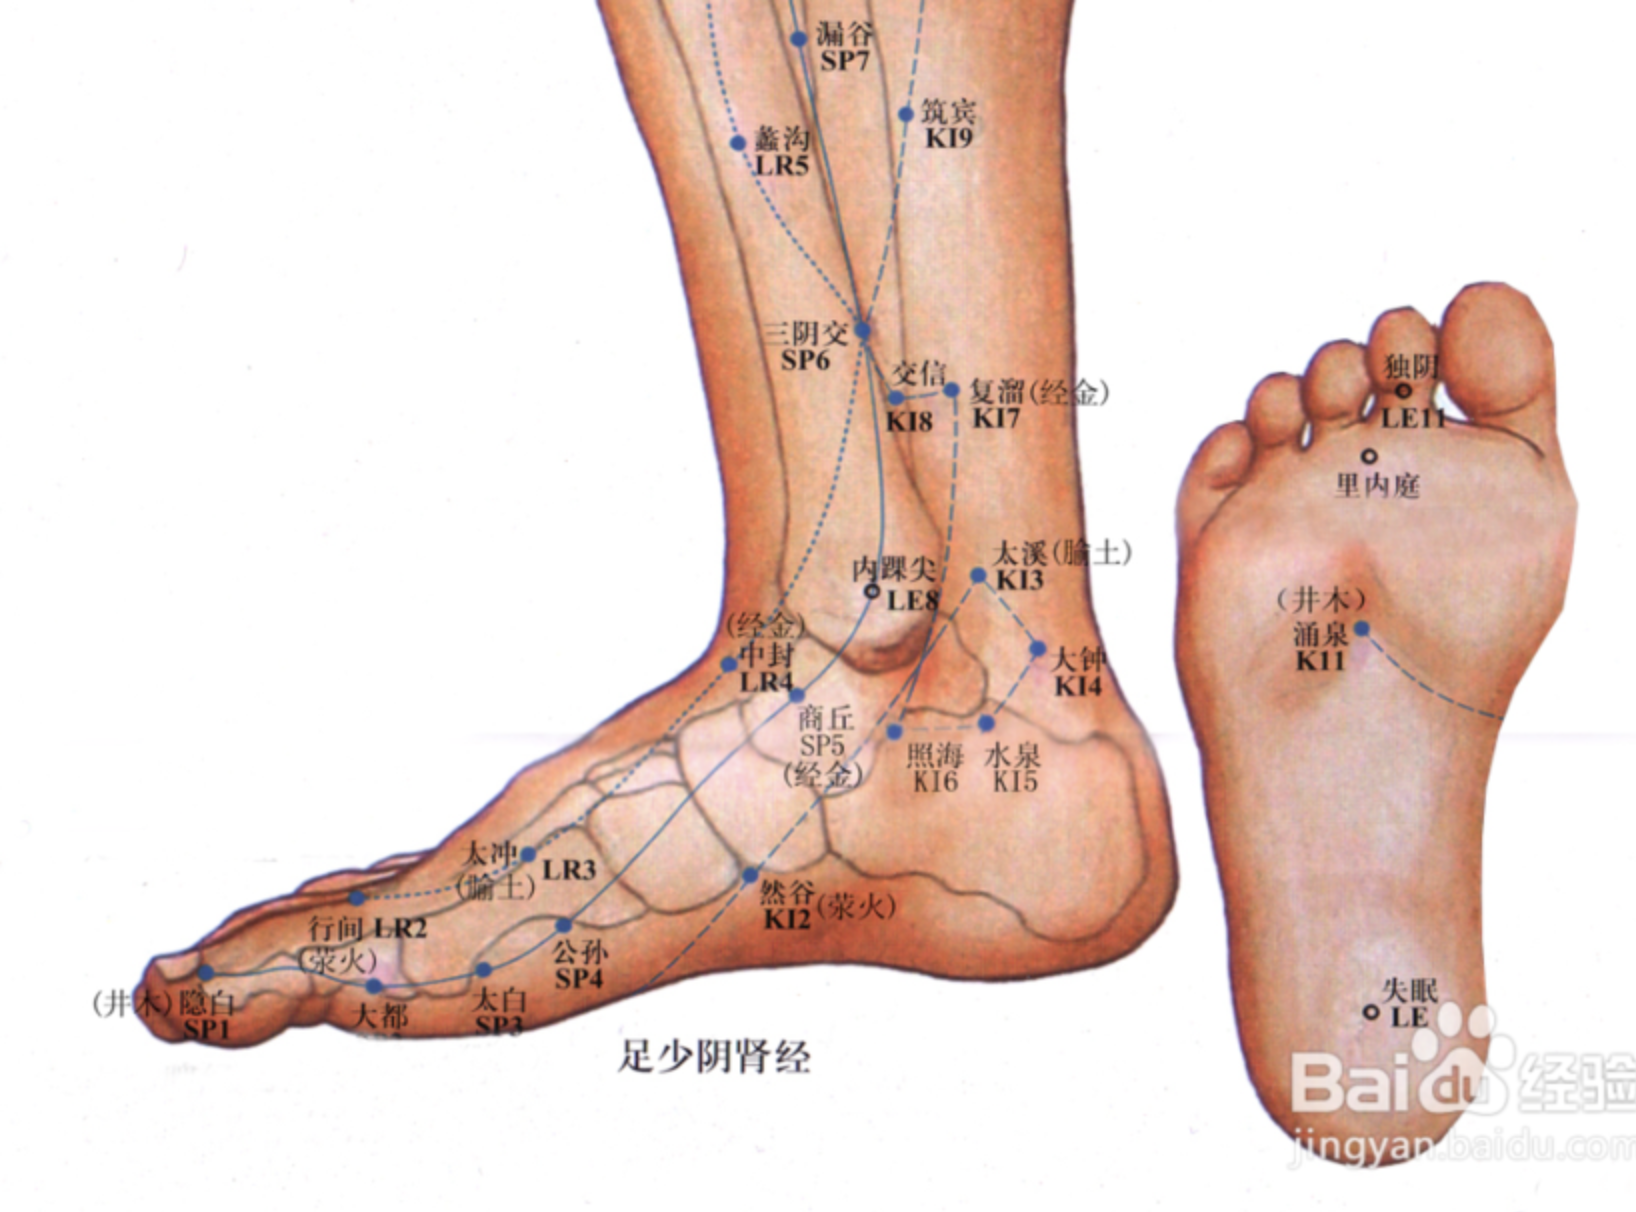

【(四)足太阴脾经(图10-22-1)】

1、时辰 巳时 9 ~ 11

2、歌诀 足太阴脾由足拇,隐白先从内侧起,大都太白继公孙,商丘直上三阴交,漏谷地机阴陵泉,血海箕(jī)门冲门前,府舍腹结大横上,腹哀食窦(dòu)天溪连,胸乡周荣大包尽,二十一穴太阴全。

3、经脉循行 起于足大趾末端(隐白),沿着大趾内侧赤白肉际,经第一跖(zhí)趾关节向上行至内踝前,上行腿肚,交出足厥阴经的前面,经膝股部内侧前缘,进入腹部,属脾络胃,过膈上行,夹咽旁系舌根,散舌下。

胃部支脉:过膈流注于心中,与心经相接。

从大趾末端开始(隐白穴),沿大趾内侧赤白肉际(大都穴),经核骨(第一骨小头后(太白穴、公孙穴),上向内踝前边(商丘穴),上小腿内侧,沿胫骨后(三阴交穴、漏谷穴),交出足厥阴肝经之前(地机穴、阴陵泉穴),上膝股内侧前边(血海穴、箕门穴),进入腹部(冲门穴、府舍穴、腹结穴、大横穴;中极穴、关元穴,属于脾,络于胃(腹哀穴;会下脘穴、日月穴、期门穴),通过膈肌,夹食管旁(食窦穴、天溪穴、胸乡穴、周荣穴;络大包;会中府穴),连舌根,散布舌下。

它的支脉:从胃部分出,上过隔肌,流注心中,接手少阴心经。

4、主要病候 胃脘痛、食则呕,嗳气,腹胀便溏,黄疸,身重无力,舌跟强痛,下肢内侧肿胀,厥冷。

5、主治概要 主治脾胃病,妇科,前阴病及经脉循行部位的其他病证。

隐白

【定位】 在足大趾末节内侧,距趾甲角 0.1 寸(图 10-22-2)。

【主治】 腹胀,便血,尿血,月经过多,崩漏,癫狂,多梦,惊风。

【配伍】 配地机、三阴交治疗出血症。

【刺灸法】 浅刺 0.1 寸。

【附注】 足太阴经所出为“井”。

公孙

【定位】 在足内侧缘,当第 1 跖骨基底部的前下方(图 10-22-2)。

【主治】 胃痛,呕吐,腹痛,泄泻,痢疾。

【配伍】 配中脘、内关治胃酸过多、胃痛。

【刺灸法】 直刺 0.6 ~ 1.2 寸。

【附注】 足太阴经络穴:八脉交会穴之一,通于冲脉。参考资料:①据报道,对消化性溃疡病人进行 X 线胃肠检查时,观察到针刺内关、足三里对胃蠕动多有增强作用,尤以足三里为明显,而针刺公孙则胃蠕动多减弱。②据报道,针刺公孙、内关、梁丘等穴有抑制胃酸分泌作用。

三阴交

【定位】 在小腿内侧,当足内踝尖上 3 寸,胫骨内侧缘后方(图 10-22-3)。

【主治】 肠鸣腹胀,泄泻,月经不调,带下,阴挺,不孕,滞产,遗精,阳痿,遗尿,疝气,失眠,下肢痿痹,脚气。

【配伍】 配足三里治肠鸣泄泻,配中极治月经不调,配子宫治疗阴挺,配大敦治疝气,配内关、神门治失眠。

【刺灸法】 直刺 1 ~ 1.5 寸。

【附注】 (1)足太阴、少阴、厥阴经交会穴。(2)孕妇禁针。

阴陵泉

【定位】 在小腿内侧,当胫骨内侧髁(kē)后下方凹陷处。

【主治】 腹胀,泄泻,水肿,黄疸,小便不利或失禁,膝痛。

【配伍】 配肝俞、至阳治黄疸,阴陵泉透阳陵泉治膝痛。

【刺灸法】 直刺 1 ~ 2 寸。

【附注】 足太阴经所入为“合”。

血海

【定位】 屈膝,在大腿内侧,髌(bìn)骨内上缘上 2 寸,当股四头肌内侧头的隆起处(图 10-22-4)。

简便取穴:患者屈膝,医者以左手掌心按于患者右膝髌骨上缘,2 至 5 指向上伸直,拇指约呈 45 度斜置,拇指尖下是穴。对侧取法仿此。

【主治】 月经不调,崩漏,经闭,瘾疹,湿疹,丹毒。

【配伍】 配三阴交治月经不调,配曲池治瘾疹。

【刺灸法】 直刺 1 ~ 1.5 寸。